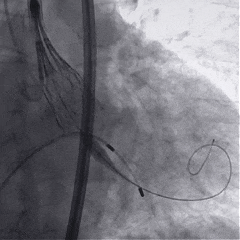

术中影像

根部造影

球囊预扩

瓣膜稳定释放

瓣膜展开后造影

再次造影,确认瓣膜位置

稳定脱钩

最终造影,瓣膜位置良好,无明显瓣周漏

外周血管检查